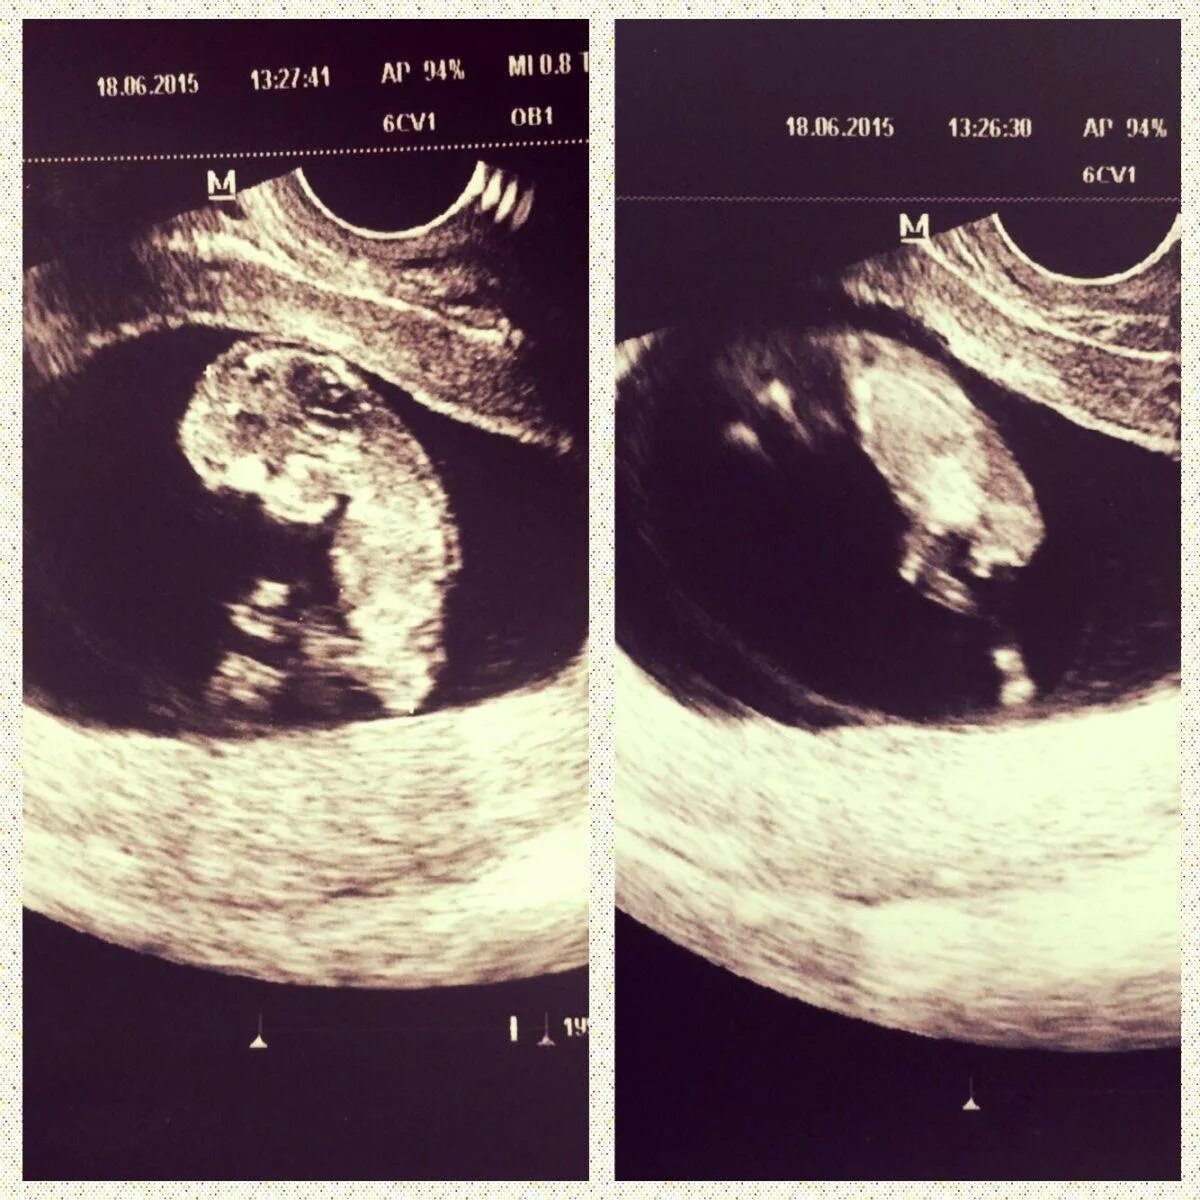

12 недель и два дня